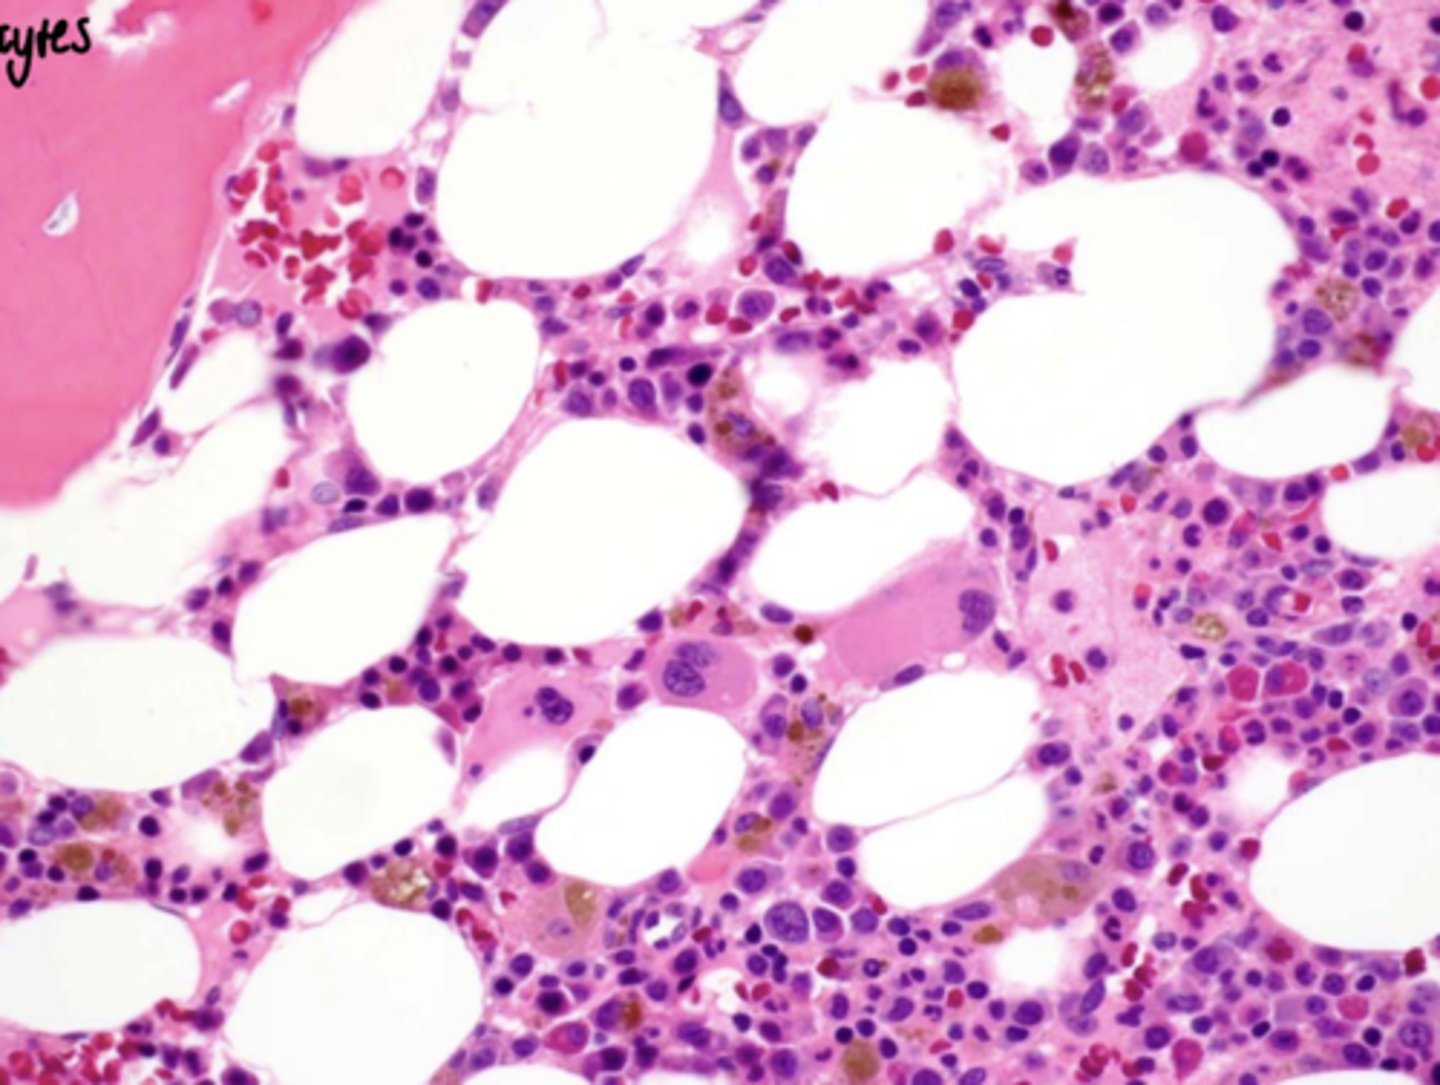

Focal osteoporotic bone marrow defect

Focal osteoporotic bone marrow defect - histology

When biopsied, see bone marrow:

- Usually hematopoeitic BM

- Huge cells in bone marrow: Megakaryocytes